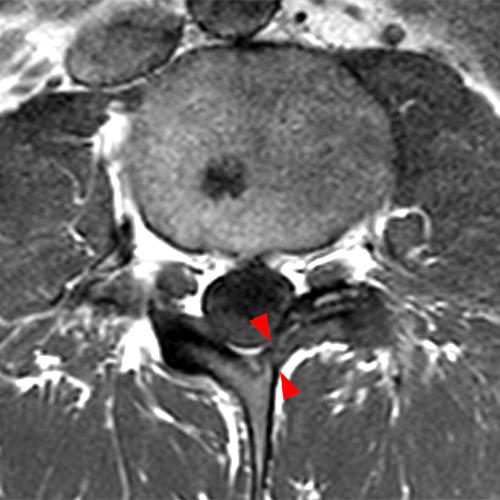

Case 2: T1-weighted (4A) and T2-weighted (4B) axial images show T1 hypointensity and T2 hyperintensity (arrowheads) in the left lamina of L5 adjacent to a small hypointense line (arrows) which traverses the lamina.

Case 2: Acute left-sided laminolysis